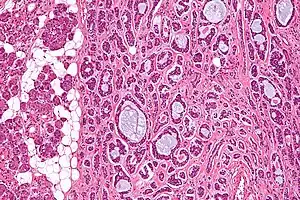

| Micrograph of an adenoid cystic carcinoma of a salivary gland (right of image): Normal serous glands, typical of the parotid gland, are also seen (left of image), H&E stain. | |

Histopathological image of adenoid cystic carcinoma of the salivary gland infiltrating a nerve (center), H&E stain